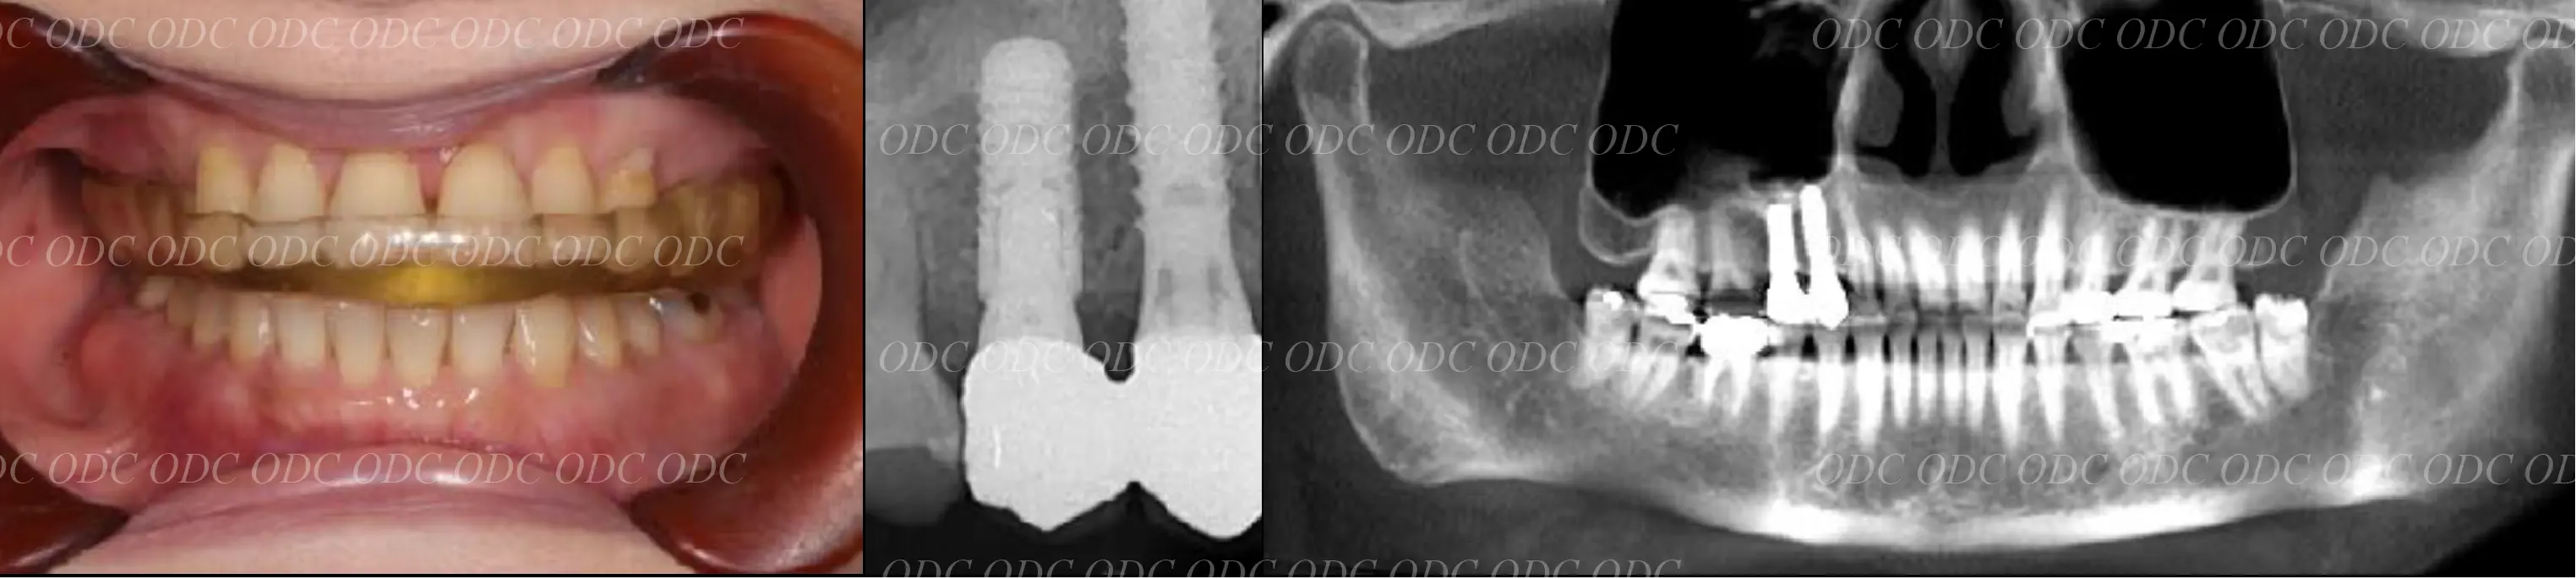

前歯部少数歯欠損症例

2014年、前歯1本欠損でインプラント治療を希望されて来院されました。

サージカルガイドを作成しインプラント埋入を行っていきました。

骨造成 結合組織移植等を行いながら最終印象を行っていきました。

最終補綴装着後の口腔内写真です。自然な仕上がりにご満足頂いております。